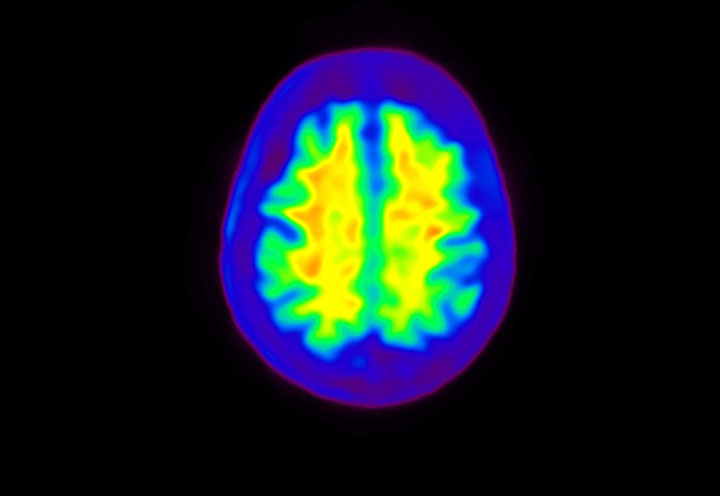

Head / Case4 : Amyloid

Axial

Courtesy : Kindai University Hospital

- Imaging protocol

- Injected dose: 3.21 MBq/kg, 18F-Flutemetamol

- Uptake time: 100 minutes

- Scan time: 20 minutes